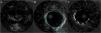

An invasive coronary angiography was performed, which confirmed the extrinsic compression of the LMCA due to dilation of the main PA (Figure 4a). An intravascular ultrasound (IVUS) was carried out (Figure 5b) to visualize the LMCA dimensions. Angioplasty was performed, placing a 4 mm×9 mm sirolimus-coated stent in the proximal and middle segments of the LMCA. The procedure was uneventful, with excellent angiographic results, documented by CTCA and IVUS (Figures 4b and 5c). The patient reported resolution of angina symptoms and relief from fatigue. Approximately one year after the procedure, despite the absence of symptoms, we decided to perform a CTCA of the coronary arteries, essentially to reassess the patency of the previously implanted stent. Normal positioning and normal conformability were observed (Figure 6), and additional compression-associated changes were ruled out. Approximately three years after coronary intervention, the patient remains clinically stable, with no recurrence of complaints of chest pain.